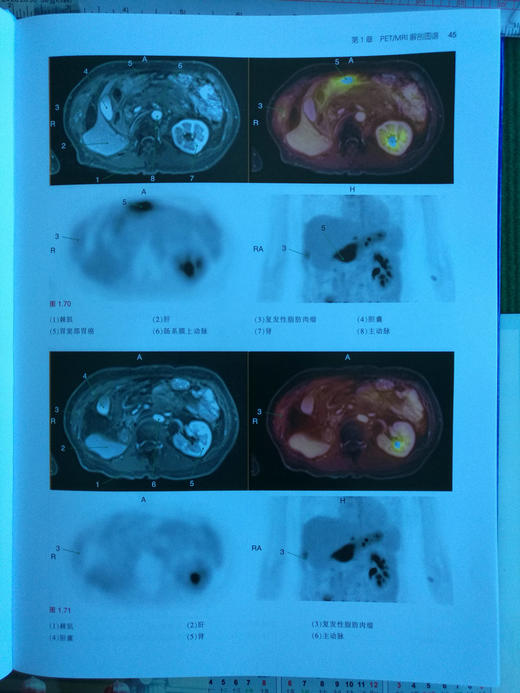

《PET/MRI, PET/CT及SPECT/CT解剖图谱》是目前融合医学影像的经典著作,书中既讲解了基础解剖内容,又有丰富的病例介绍。全书共3章内容,分别为PET/MRI解剖图谱、PET/CT解剖图谱和SPECT/CT解剖图谱。第1章PET/MRI解剖图谱按照大脑、头颈部、胸部、腹部、盆腔、肌肉骨骼系统进行描述。第2章PET/CT解剖图谱按照FDG和非-FDG进行分类描述。第3章则描述了肿瘤、骨和其他病变的SPECT/CT表现。本书编者临床经验丰富、理论基础扎实、科研能力出众,以“融合图像”作为突出特色,荟萃了当今最为先进的PET/CT、PET/MRI及SPECT/CT技术,有助于提升国内从业人员的专业素养、优化诊断思路,进而更好地服务于患者。